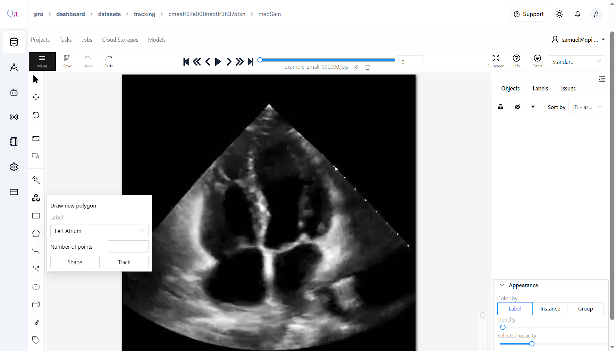

Click âAnnotationâ in the toolbar.

- Select âDraw New Polygonâ from the available options.

- On the displayed image, click to place points around the target area, forming a polygon that outlines the region of interest.

- Ensure that each polygon corresponds to the classes you defined during dataset creation, providing accurate visual prompts for segmentation.

- Continue to draw polygon points for the classes you want to annotate manually.